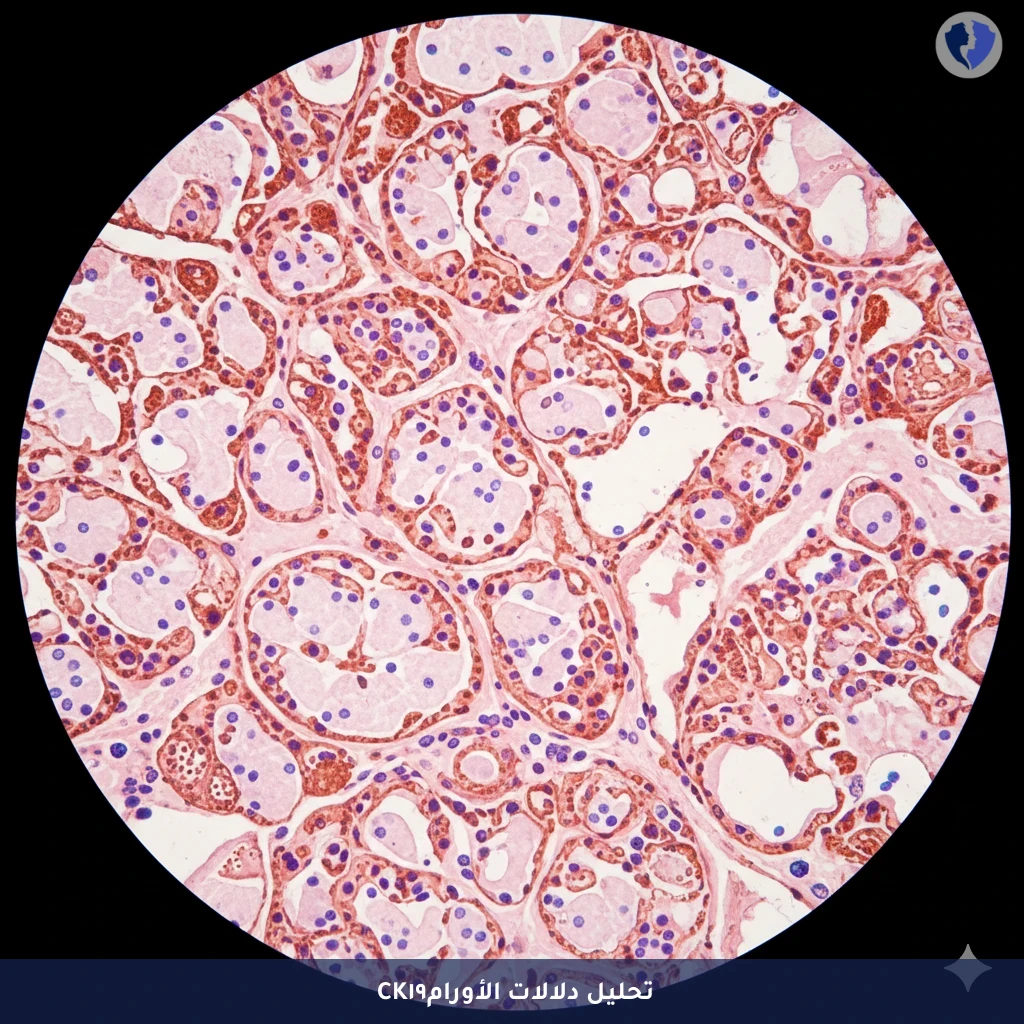

فحص الكيمياء الهيستولوجية المناعية لـ CK19 (سيتوكيراتين 19) يهدف إلى الكشف عن هذا النوع الخاص من الكيراتين (الخيوط المتوسطة) منخفض الوزن الجزيئي. يعتبر CK19 علامة عالية الحساسية للتعبير في معظم السرطانة (Carcinomas)، وخاصة السرطانة الغدية (Adenocarcinoma)، ويستخدم على نطاق واسع في تقنيات مثل الخزعة الحالّة للعقدة الخافرة (SLNB) في سرطان الثدي وفي تقييم انتشار الورم إلى نخاع العظم.